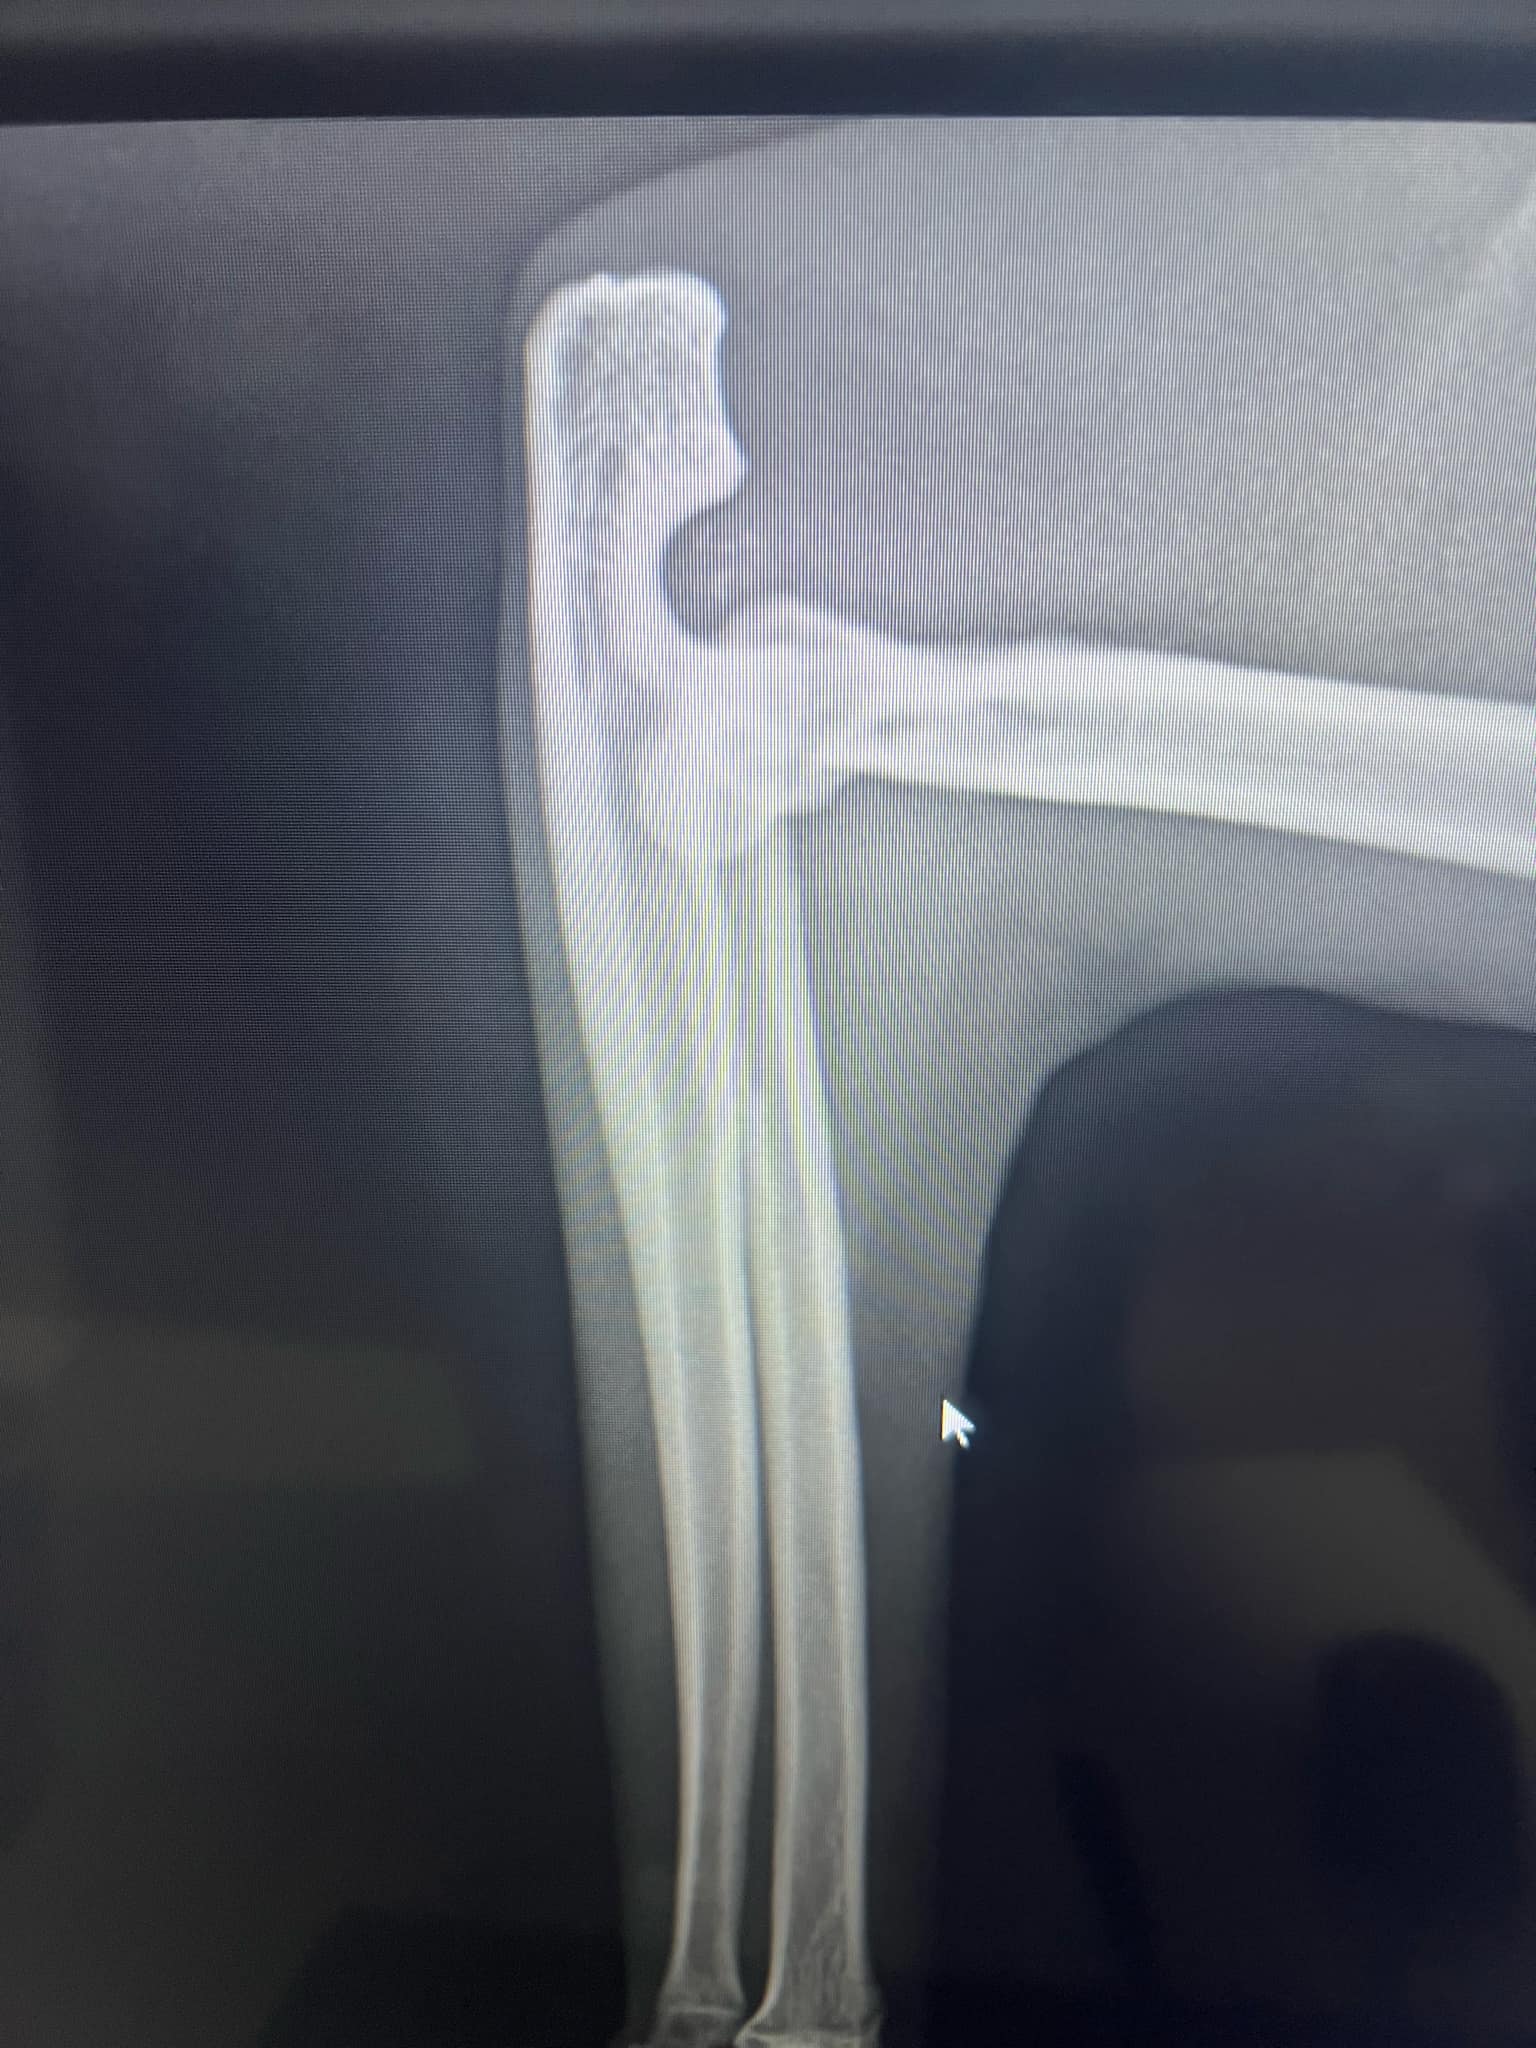

Jego łapka była prawdopodobnie zmiażdżona, a kosteczki paluszków połamane (widać na zdjęciach rtg). Dodatkowo miał złamanie (wyrwanie) kości łokciowej.

W pierwszej kolejności kotek został zoperowany w Davet Radłów przez dr Mączkę. Łapka została pozszywana, kotek miał naświetlania i żelowe opatrunki, tak aby przyspieszyć gojenie. Następnie Zeus przeszedł operację łokcia w ArWet w Wieliczce. Kotek został też wykastrowany.